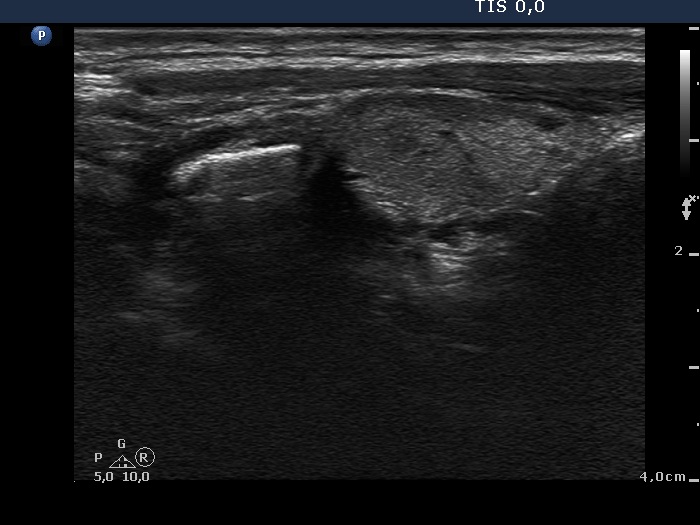

Lymph nodes - case 1096 (ultrasonographic picture 2)

Upper part of the right lobe, longitudinal view.